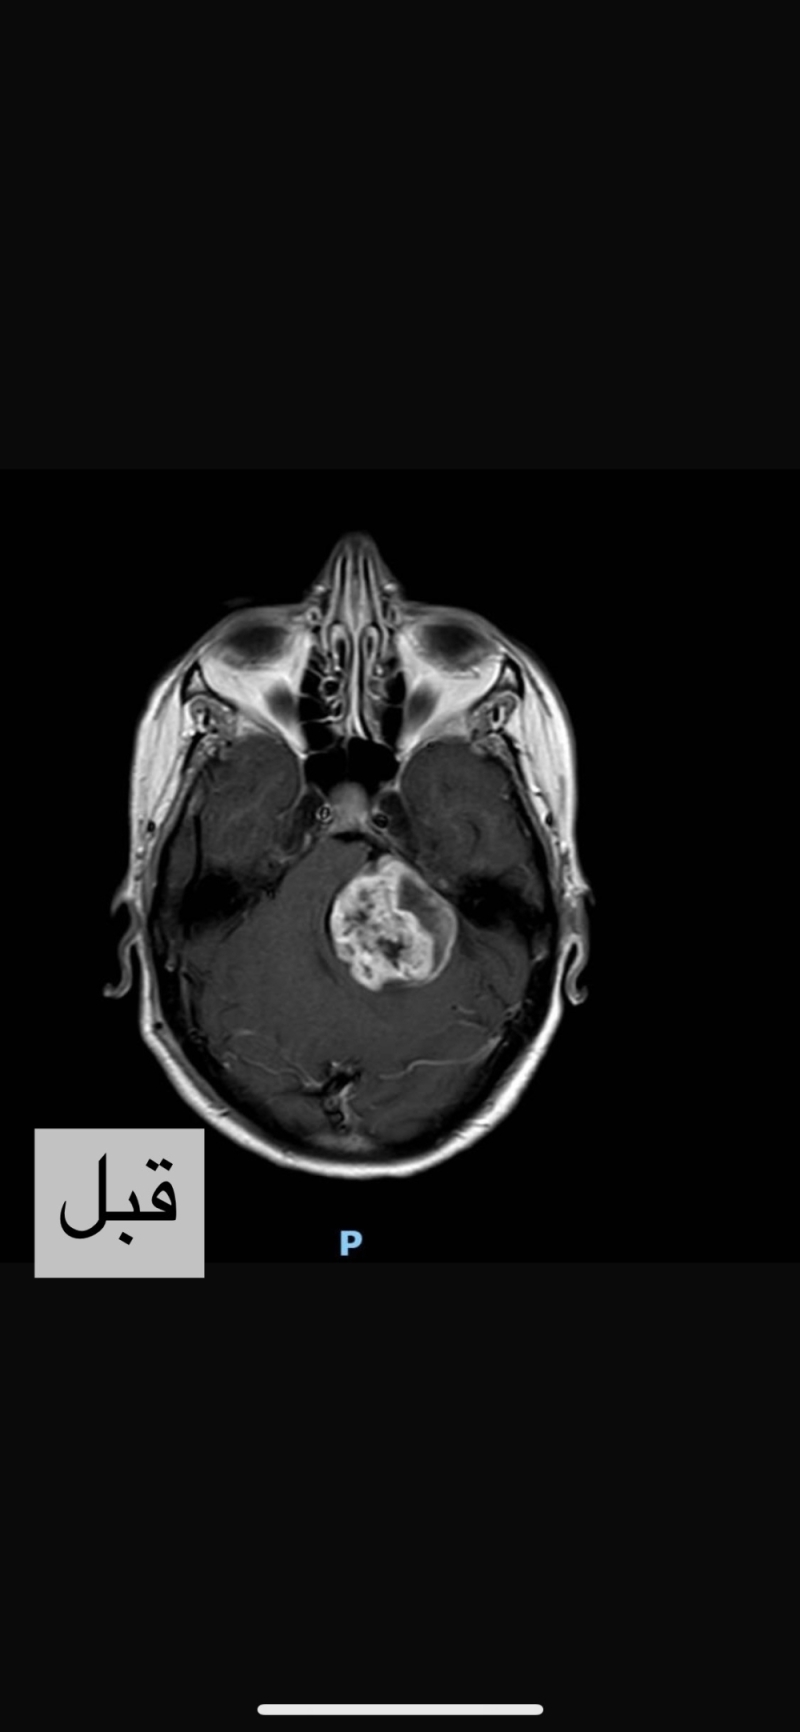

بحمدالله وتوفيقه، تمكن الفريق الطبي في مستشفى المواساة بالدمام من إجراء جراحة خطيرة ونادره لاستئصال ورم ضخم تعدى قطره ٥ سم بقاع الجمجمة بالحجرة الخلفيه للمخ.

حيث وصلت مريضه تبلغ من العمر ٤٤ عاما محوله لمستشفى المواساة بالدمام، وأكدت الفحوصات الجراحية الكاملة مزيداً من الدلائل على الحالة .

وبإشراف الدكتور عمر الفلكي، استشاري جراحة المخ و الأعصاب، و فريقه الجراحي تم إستئصال الورم بالكامل في جراحة ميكروسكوبية دقيقة استغرقت أكثر من ١٠ ساعات تم فيها استخدام جهاز الملاح الجراحي و المراقبة المستمرة للوظائف الحركية طوال فترة الجراحة .